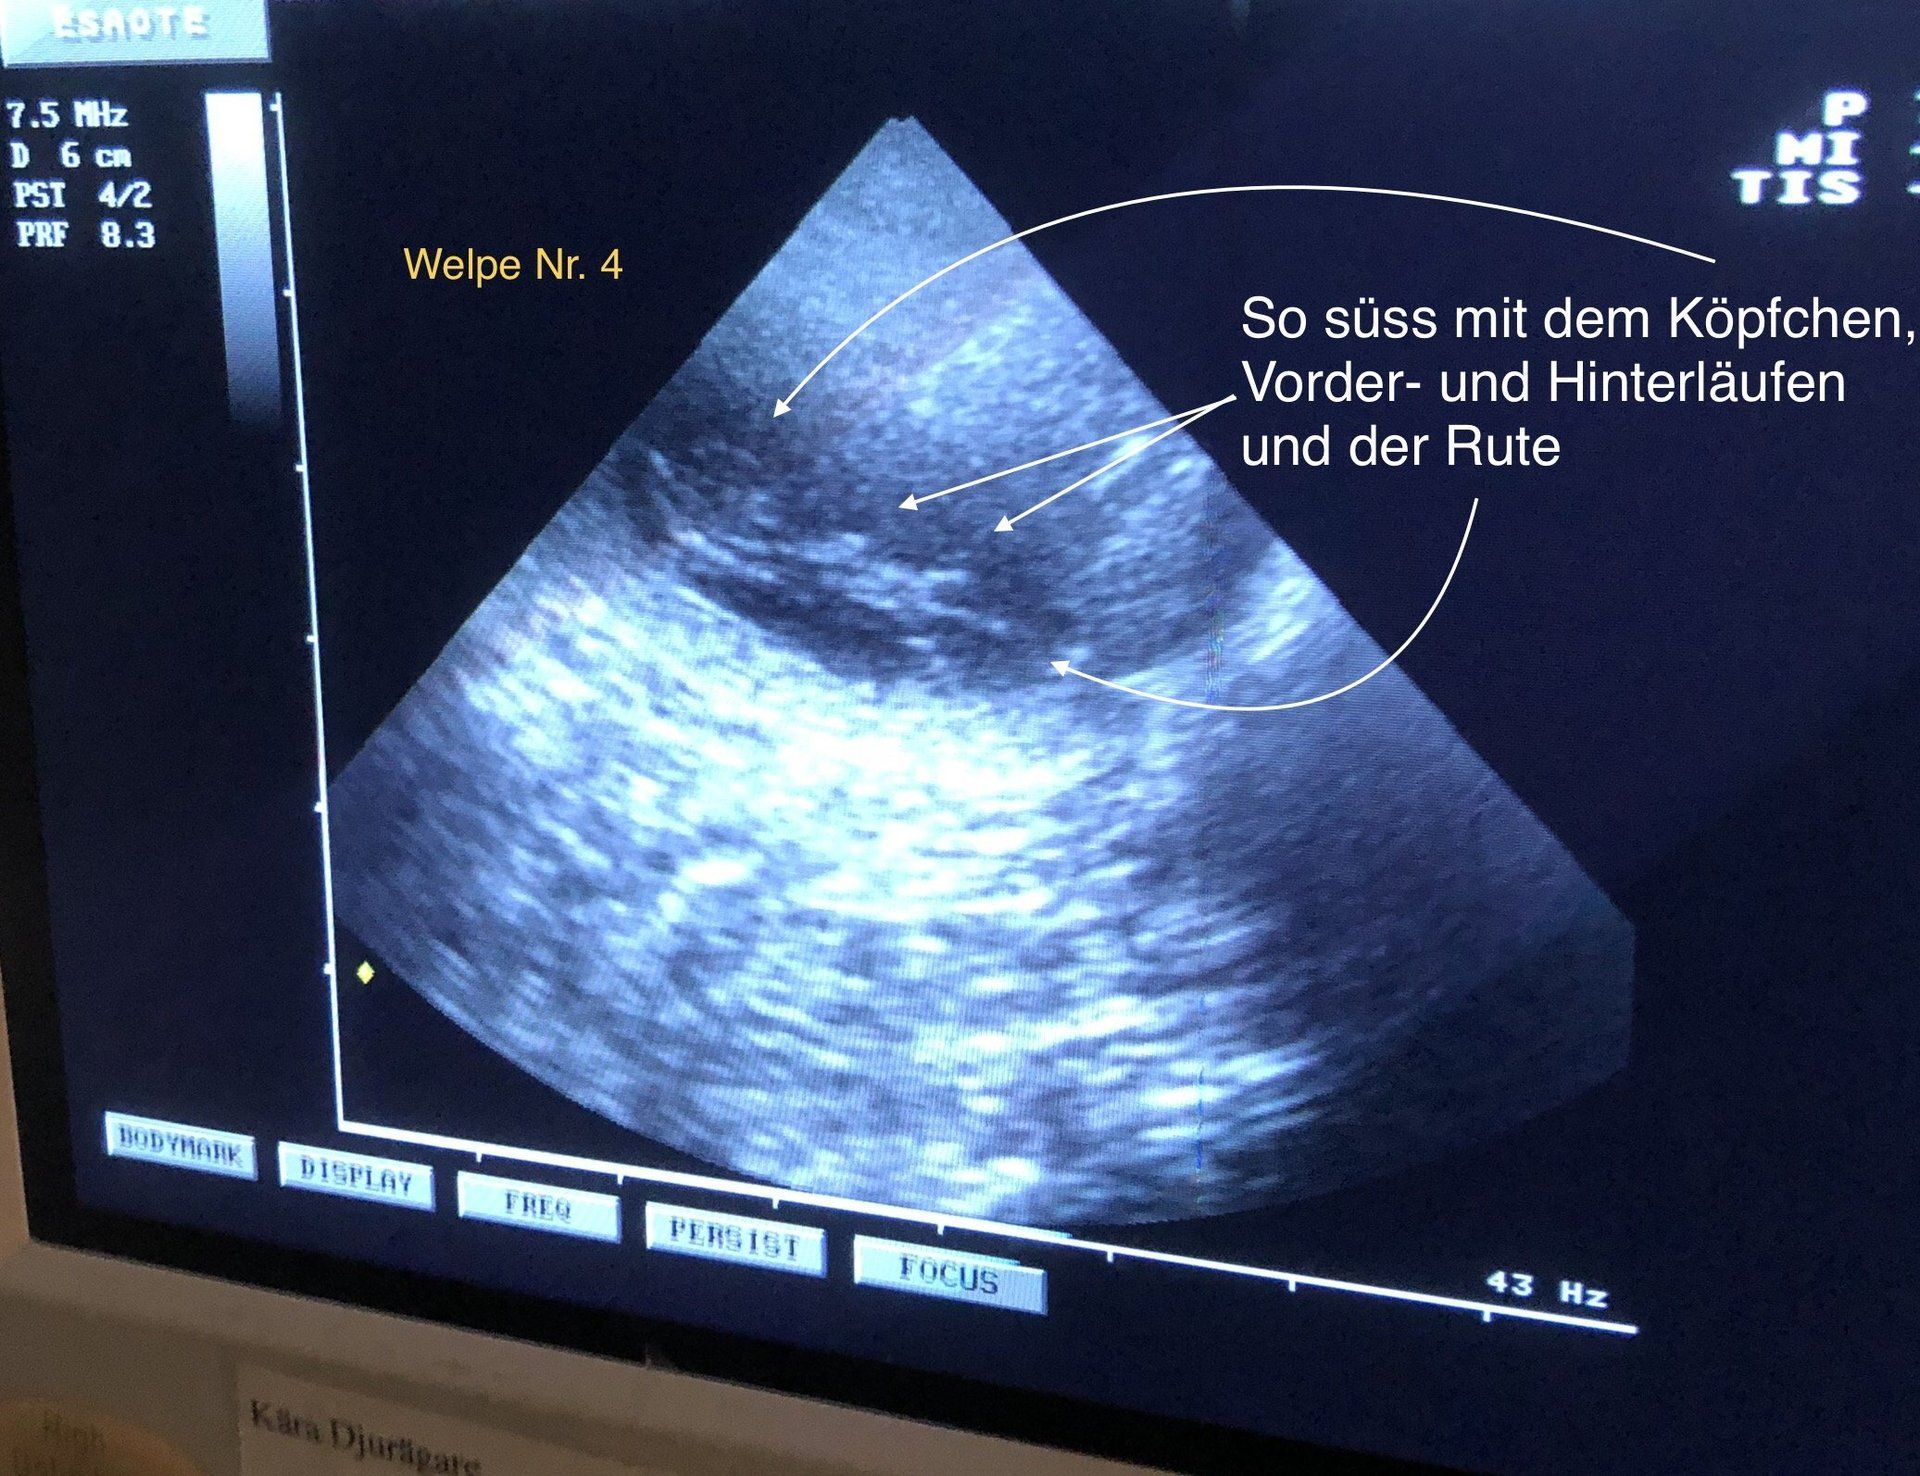

Nachdem Alva so massiv Trächtigkeitsanzeichen hatte, bin ich heute noch einmal zum TÄ gefahren. Hier wollte ich eine mögliche Einfrüchtigkeit ausschließen, da dies zu Problemen bei der Geburt führen kann.

Aber hier wurde dann auch der letzte kleine Hoffnungsschimmer auf wenigstens 1-2 Welpen weggewischt. Alva hat definitiv keine(n) Welpen. Sie bekommt jetzt etwas Globolie gegen die Scheinträchtigkeit. Sie hat in den letzten Tagen sehr mäkelig gefressen und zum Teil die 1/2 auch wieder 🤮.

Allen Welpeninteressenten habe ich jetzt eben per Mail ganz offiziell abgesagt, trotz das ich bei dem negativen Ultraschallergebniss schon bescheid gegeben hatte. Auch dem DRC habe ich die Wurfmeldung mit dem X bei "meine Hündin ist leer geblieben" schon geschickt. Was fertig ist, ist fertig 🤷🏻♀️.

Heute war der lang ersehnte Termin bei unserer TÄ.

Leider war bei dem Untersuchungs-Termin das Ergebnis nicht wie erhofft 😢. Alle Bemühungen 🥰 von Basko sind scheinbar erfolglos geblieben. Alva ist nicht trächtig. Lars und ich sind Beide enttäuscht, aber änderns kann man es nicht.

Wir werden die Woche noch einmal zur TÄ fahren, um Alva abklären zu lassen. Basko ist ja gerade noch mal Papa geworden, so dass es nicht an ihm liegt/lag....

Irgendwie war ja Alva beim Decken schon extrem empfindlich (Teilweise beim Aufreiten gequietscht), so dass wir da schon eine erneute Abklärung gemacht hatten. Da war aber ihre alte Verletzung nach einer Drückjagd Anfang 2020 als Ursache diagnostiziert worden. Aber jetzt.... Sie läuft anders, humpelt zum Teil, schläft nur, will sich nicht bewegen und verhält sich allgemein super anders. Da Alva eigentlich nie wirklich scheinträchtig war, hat sie entweder alle Welpen super gut versteckt oder es ist etwas anderes im Busch....

Aber es ist wie es ist und ich hoffe jetzt, dass Alva tatsächlich "nur" scheinschwanger ist und nichts ernstes hinter dem Verhalten steckt.

Allen Welpeninteressenten muss ich leider absagen. Ich drücke Euch die Daumen bei der Suche nach einem Flat-Baby!